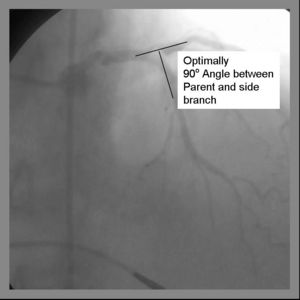

May use a 6Fr Guiding system Final Kissing balloon inflation required due to high Restenosis rate Ideal angle of bifurcation is at or near 90 degrees.

2) Both the parent and side branch are wired. Predilation is recommended to ensure optimal balloon expansion and ease stent delivery. It is important to identify which wire is placed in which branch. We recommend either using 2 separate colored guide wires, keeping a marker on 1 wire, or covering a wire with a sterile towel while not in use.